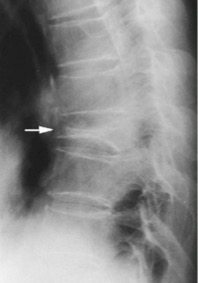

Solitary collapsed vertebra/ Vertebra Plana:

Differentials include:

- Trauma

- Infection

- Osteoporosis

- Langerhans cell histiocytosis

- Metastases

- Multiple myeloma

- Lymphoma

3. Reporting format for frontal and lateral radiographs of the lumbar spine with compression fracture

Findings:

There are five non-rib bearing lumbar type vertebrae. There is an approximately 30% superior endplate wedge compression fracture of L1 with retropulsion of the posterior superior endplate likely contributing to mild canal narrowing. Alignment is maintained. The paraspinal soft tissues are unremarkable.

Impression:

30% superior endplate wedge compression fracture of L1 with posterior superior endplate retropulsion contributing to mild canal narrowing.